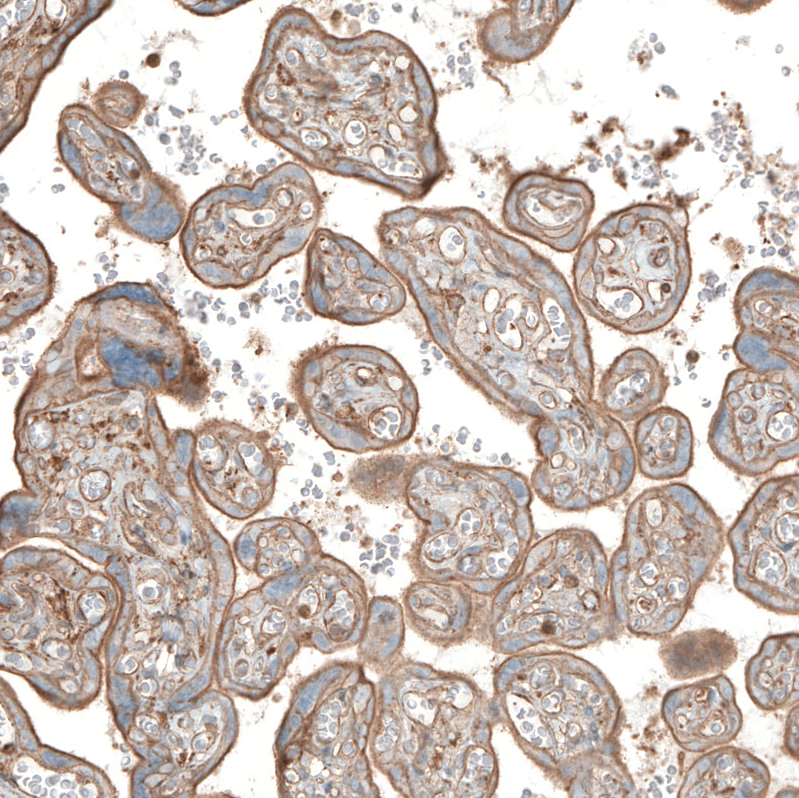

Immunohistochemical staining of human smooth muscle shows moderate positivity.